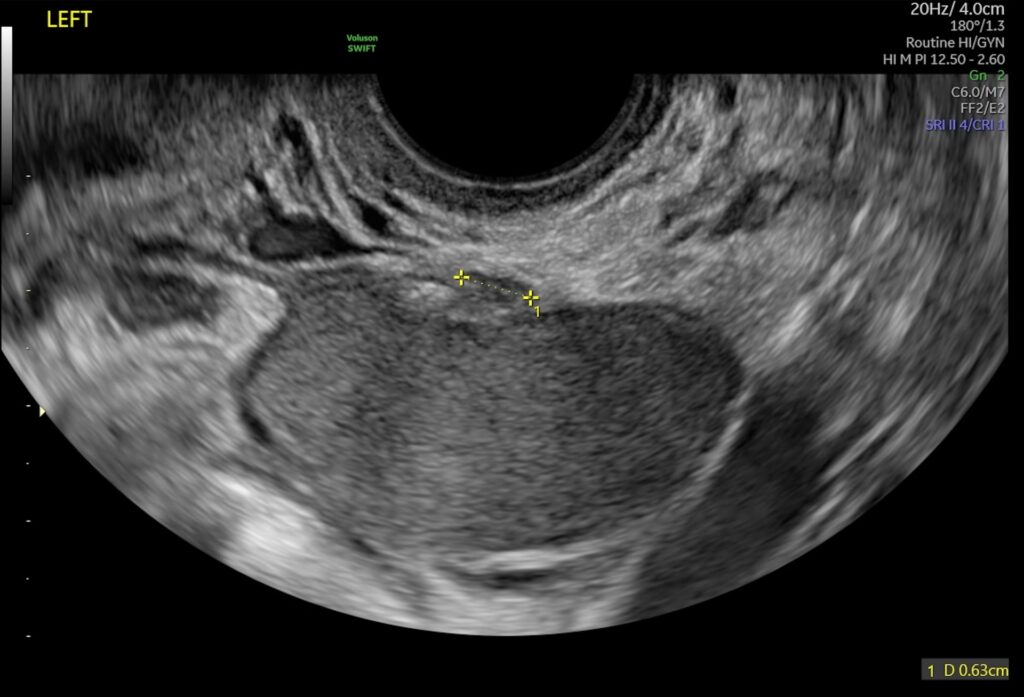

Den transvaginale ultralydsscanning er den mest almindelige og detaljerede metode til diagnosticering af endometriose. Under denne procedure føres en lille, specialdesignet ultralydsprobe forsigtigt ind i skeden. Dette giver en meget tæt og klar visning af bækkenorganerne, herunder livmoderen, æggestokkene og æggelederne. Metoden producerer billeder i høj opløsning, der tydeligt kan afsløre endometriomer og vurdere involveringen af æggestokkene og de omkringliggende strukturer. Fordi proben er så tæt på organerne, kan den opdage selv små forandringer, som en abdominal scanning ville overse.

Et af de mest genkendelige tegn på endometriose ved en ultralydsscanning er tilstedeværelsen af endometriomer. Disse er væskefyldte cyster på æggestokkene, ofte kaldet "chokoladecyster", fordi de er fyldt med gammelt, mørkt blod, der ligner smeltet chokolade. På en ultralydsscanning ses endometriomer typisk som velafgrænsede, runde strukturer med et homogent, lav-ekko mønster (mørkt) indeni. Deres karakteristiske udseende gør dem relativt lette at identificere for en erfaren sonograf.